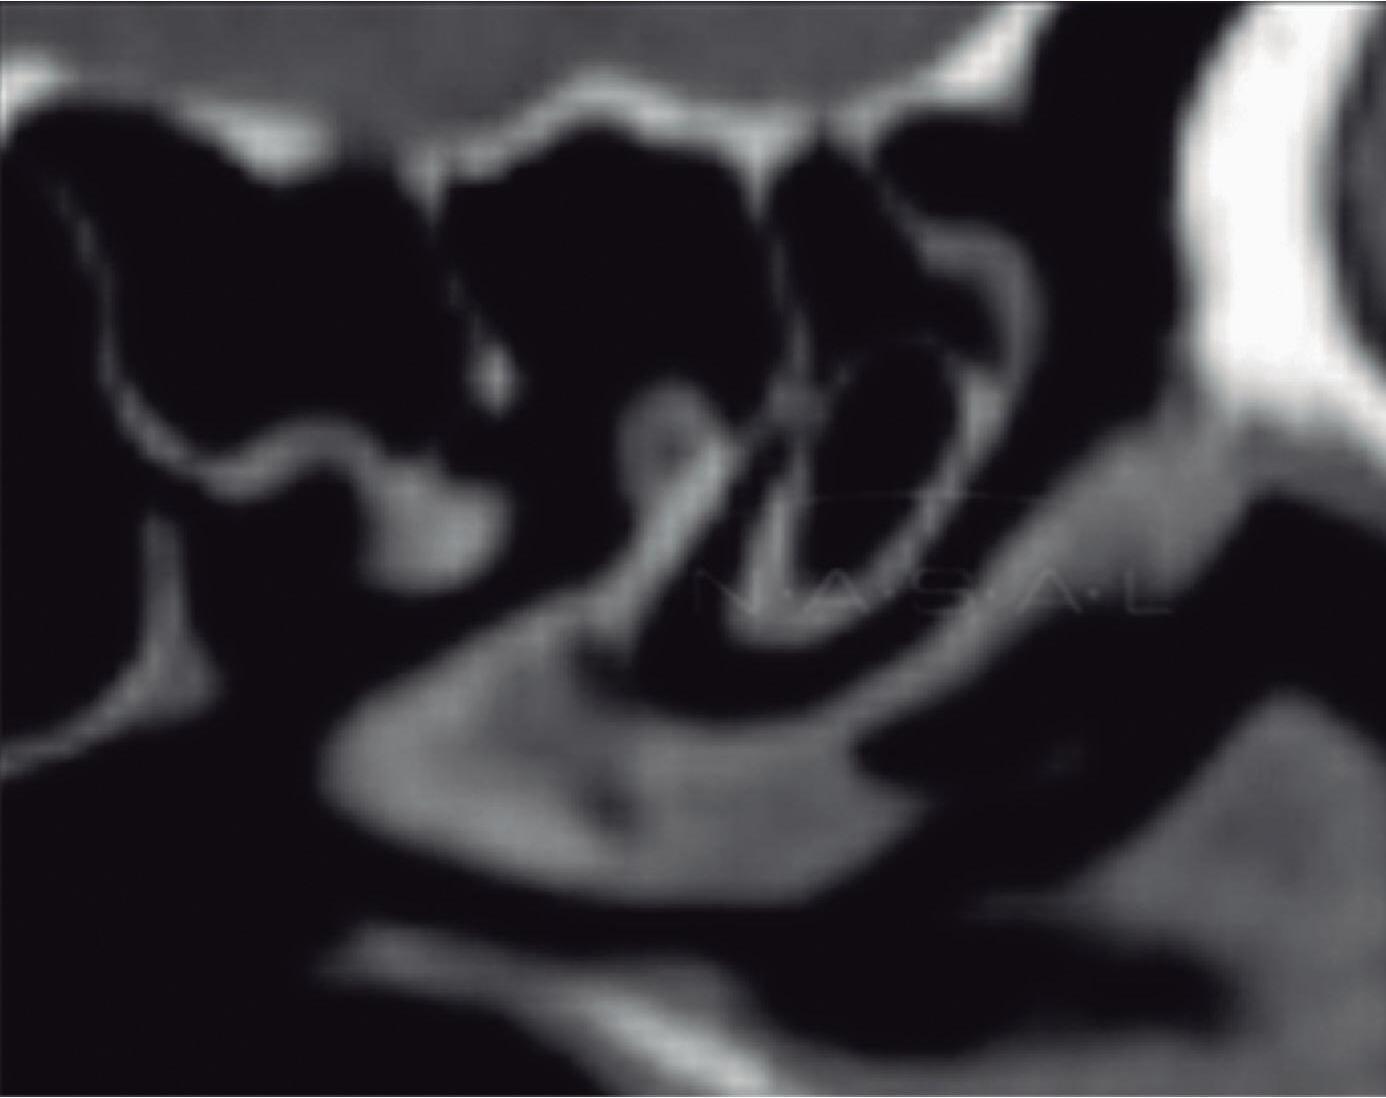

Fig. 1-20. Reconstrução tridimensional de TC demonstrando a lamela basal situada posteriormente à bulha etmoidal, acoplada à parede medial da órbita, fechando a câmara anterior: verde – concha média; vermelho – bulha etmoidal; amarelo – parede medial da órbita; lilás – processo uncinado.

A lamela basal da concha média é a parede anterior do meato superior que é limitado posteriormente pela lâmina basal da concha superior, que será o limite anterior do meato supremo que vai ser limitado posteriormente pela face anterior e lateral do seio esfenoidal.

Cada concha tem sua lamela conectada à parede medial da órbita, mas podem também se conectar ou seguir em direção à base do crânio.